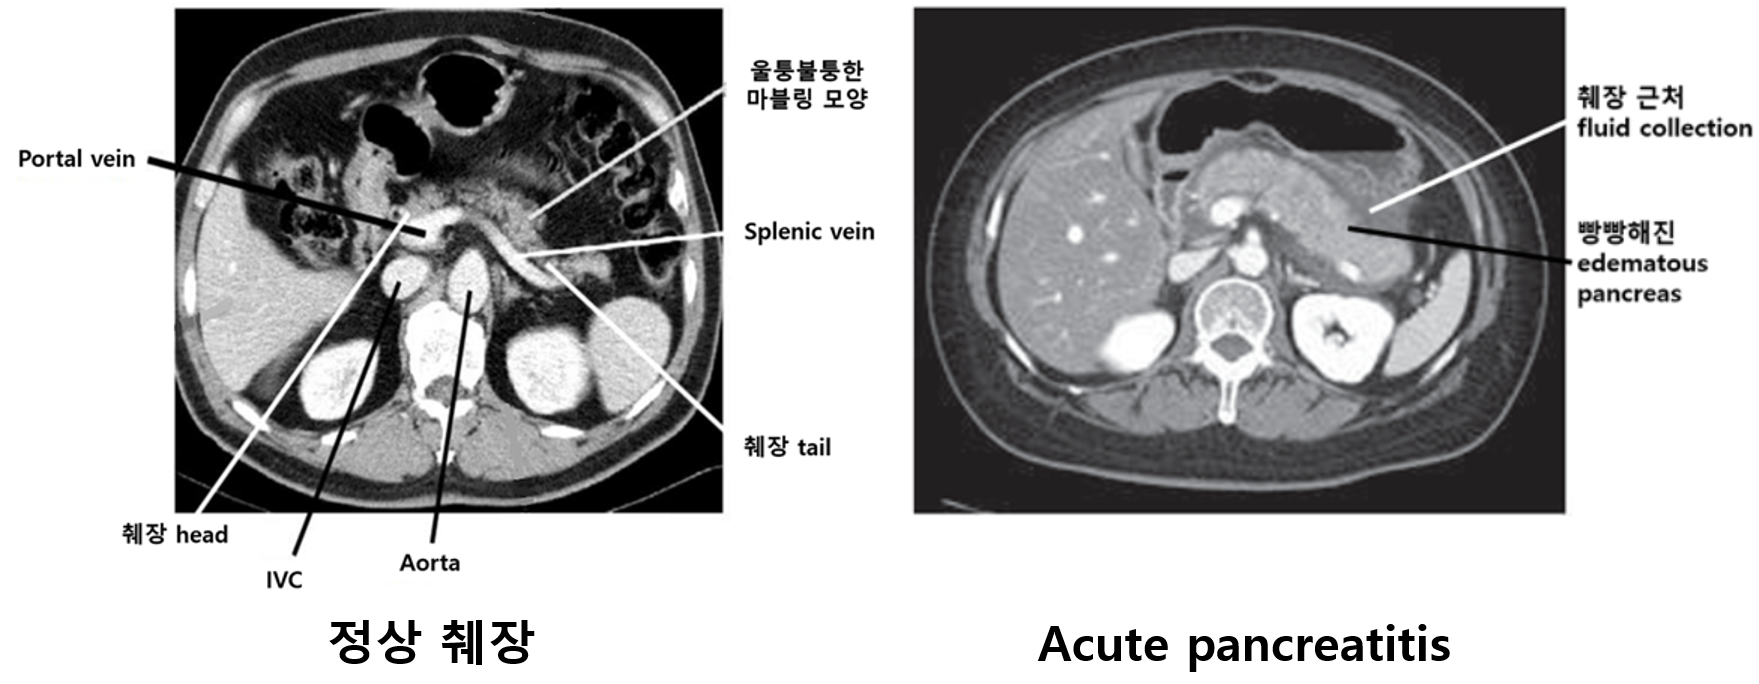

2) 복부 CT/MRI: 췌장염의 중증도 판정, 합병증 유무 확인, 기타 감별진단 배제 등을 위해 필요

췌장 실질의 edema, 췌장 근처 조직의 inflammation

• CT: 췌장 실질의 edema, 췌장 근처 조직의 inflammation